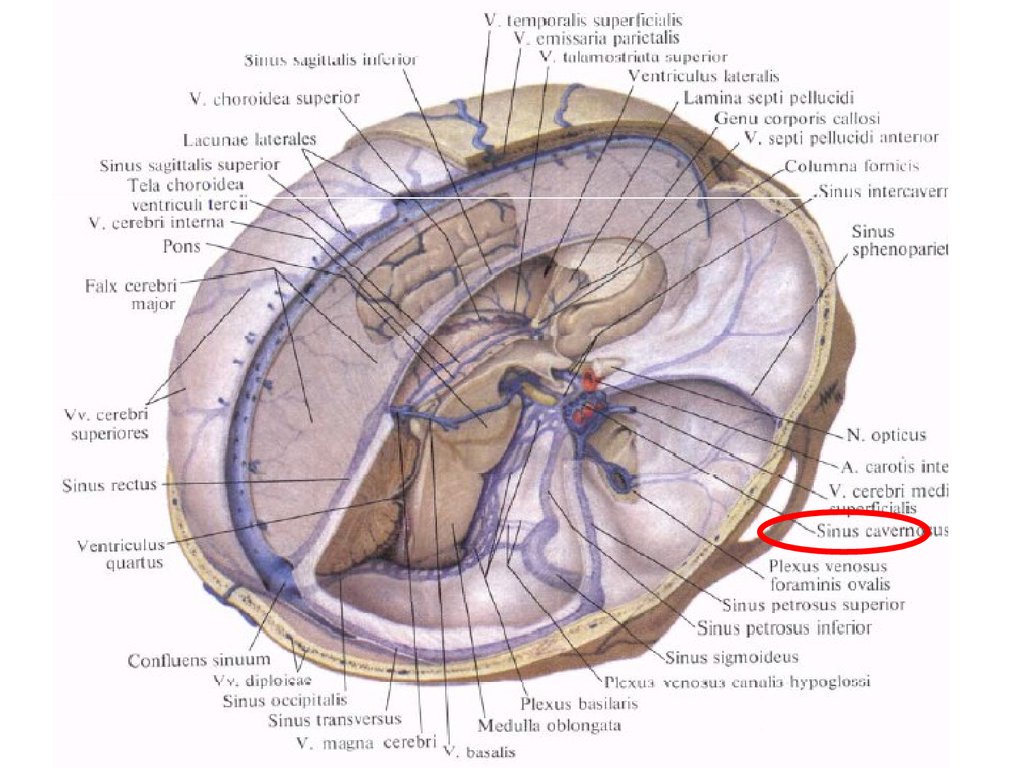

Анатомические изображения срединной сагиттальной линии черепа

Раздел: Образы вокруг